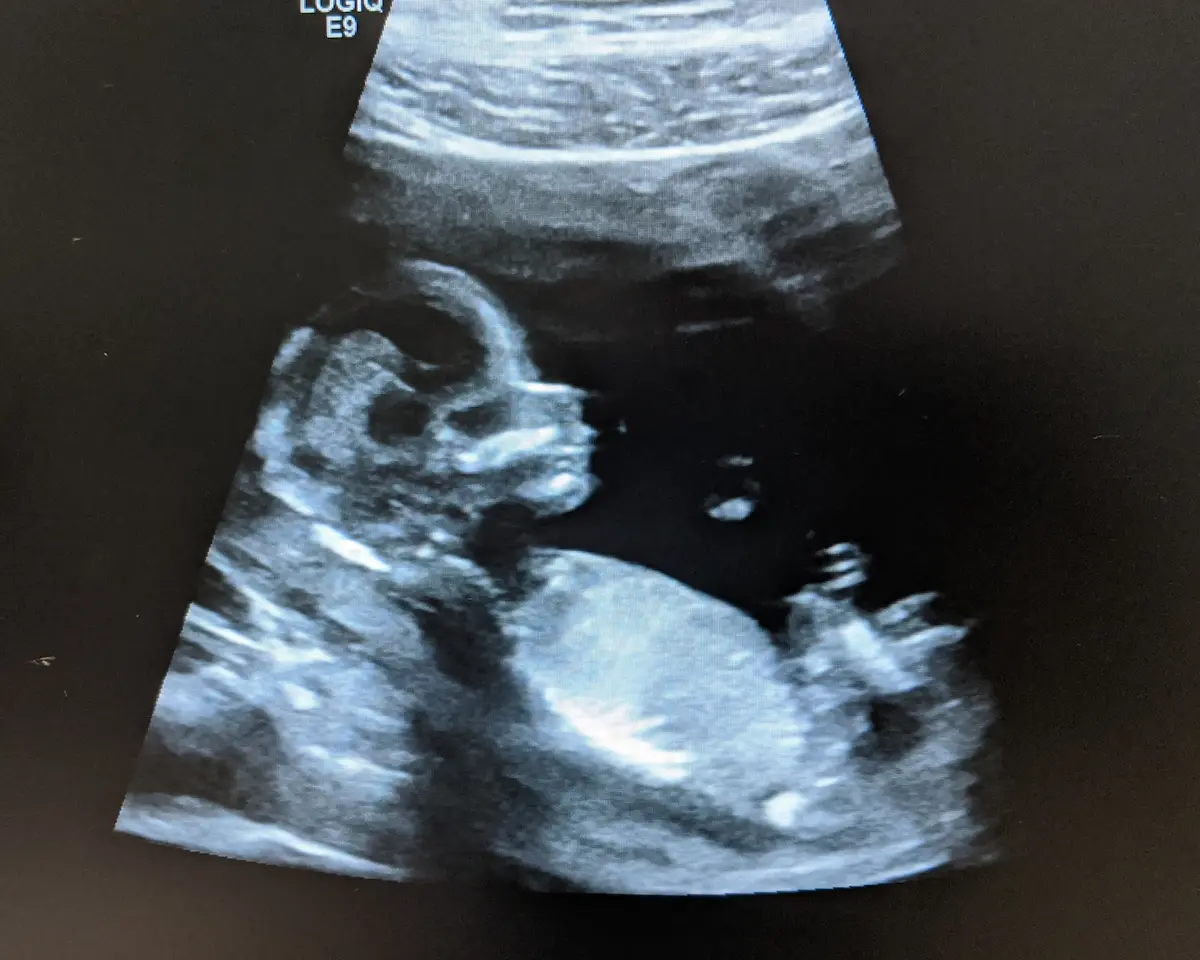

Iron helps produce haemoglobin — the molecule that carries oxygen in your blood to your baby. This supports healthy growth and development throughout pregnancy.

Iron is crucial for building the placenta — your baby’s source of nutrients and oxygen.

It also supports the expanded blood volume your body needs during pregnancy, ensuring both you and your baby receive adequate oxygenation.